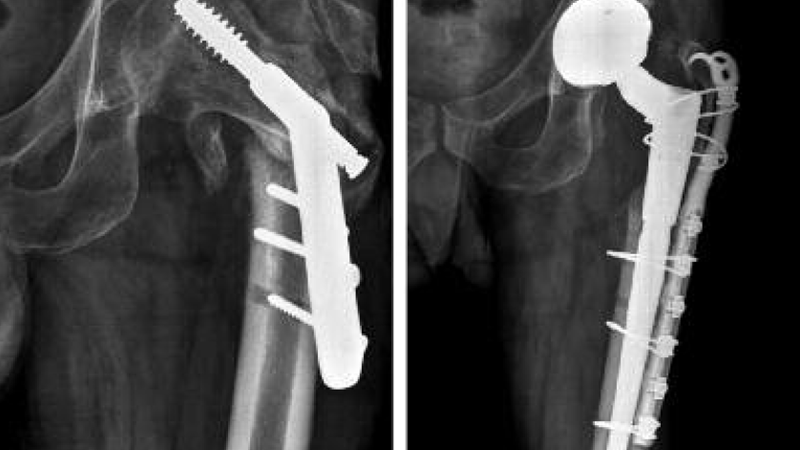

During revision hip replacement, the surgeon removes the failed or problematic components of the previous hip replacement and replaces them with new implants. This may involve using specialized revision implants, bone grafts, or other techniques to address any bone loss or structural issues. The goal is to restore stability, function, and alleviate pain.